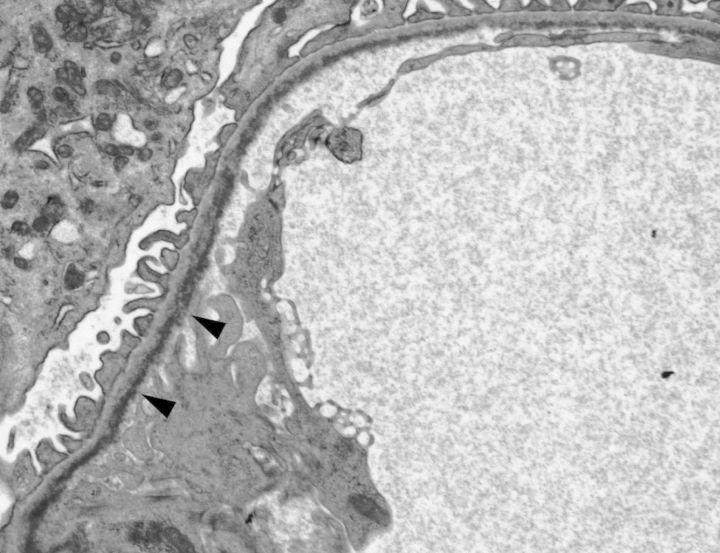

Systemic mastocytosis (SM) is characterized by infiltration of neoplastic mast cells in one or more organ systems. SM in association with plasma cell dyscrasia is very rare. We report a first case of indolent SM (ISM) associated with light chain deposition disease (LCDD) in a kidney biopsy from a 59-year-old female presenting with skin rash, elevated serum creatinine, hematuria and mild proteinuria. Subsequent workup demonstrated IgG kappa monoclonal protein in serum and urine. A bone marrow biopsy revealed neoplastic mast cells involving bone marrow without evidence of clonal myeloid or lymphoid proliferation. Kidney biopsy demonstrated modest mesangial expansion detected by light microscopy and unequivocal evidence of monoclonal kappa light chain deposition within glomerular capillaries, tubular basement membranes and vascular walls detected by immunofluorescence and/or electron microscopy, along with equivocal evidence of light chain cast nephropathy. Despite treatment with bortezomib and dexamethasone, her renal function was progressively declined over the next 6 months. This case is a reminder that SM can coincide with LCDD, which requires clinical suspicion and multimodality workup on a kidney biopsy including immunofluorescence and electron microscopy to reach the correct diagnosis.

系统性肥大细胞增多症(SM)的特征是肿瘤性肥大细胞浸润一个或多个器官系统。与浆细胞异常增生相关的SM非常罕见。我们报告了首例惰性SM(ISM)合并轻链沉积病(LCDD)的病例,该病例来自一名59岁女性的肾脏活检,患者表现为皮疹、血清肌酐升高、血尿和轻度蛋白尿。后续检查显示血清和尿液中有IgG κ单克隆蛋白。骨髓活检显示肿瘤性肥大细胞累及骨髓,无克隆性髓系或淋巴系增殖证据。肾脏活检显示,光镜检查发现系膜轻度增宽,免疫荧光和/或电子显微镜检查明确显示肾小球毛细血管、肾小管基底膜和血管壁内有单克隆κ轻链沉积,同时有轻链管型肾病的可疑证据。尽管接受了硼替佐米和地塞米松治疗,但在接下来的6个月里,她的肾功能仍逐渐下降。该病例提醒我们,SM可能与LCDD同时发生,这需要临床怀疑,并对肾脏活检进行多模态检查,包括免疫荧光和电子显微镜检查,以做出正确诊断。